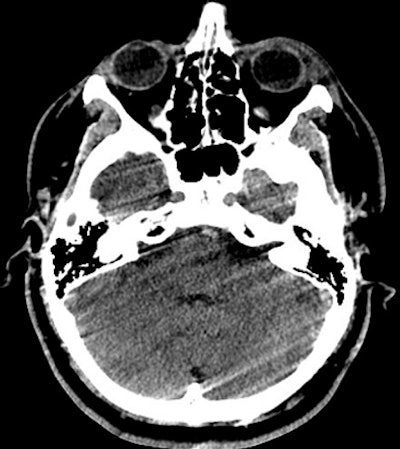

![]() |

| One slice of a posterior fossa scan that 75% of technologists and none of the radiologists chose to repeat. All images courtesy of Dr. Jaron Chong. |